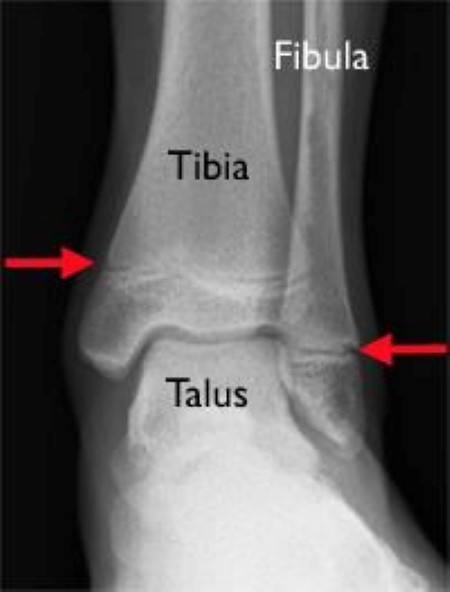

A stress fracture of the ankle also known as a hairline fracture is a small micro fracture of the bone. Ankle fracture causes when you stress an ankle joint beyond the strength of its elements you injure the joint. Stress fractures of the foot and ankle a stress fracture is a small crack in a bone or severe bruising within a bone.

Ankle fractures almost always occur during a traumatic event to the body. If only the ligaments give way and tear you have sprained the ankle. Stress fracture ankle symptoms include pain swelling and immobility.

Hairline fracture ankle healing tips if you want to speed up the process of healing refrain from doing activities. Common signs of an ankle fracture include pain swelling bruising and an inability to bear weight on the broken ankle. Hairline fractures are minute cracks on the bones which can become severe if not treated immediately.